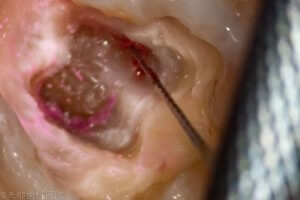

近心根は頬側根と舌側根が途中から癒合していました。歯髄腔から2本の根管が根尖部で癒合して1根尖となるVertucciの分類で言うとTypeⅡのような形状でしょうか。

近心根の舌側根と頬側根の癒合が綺麗になりました。こういった複雑な根管形状やイスムスをどこまでいじるかはいつも悩みますがCBCTと歯科用顕微鏡を用いることでなんとか対応しています。